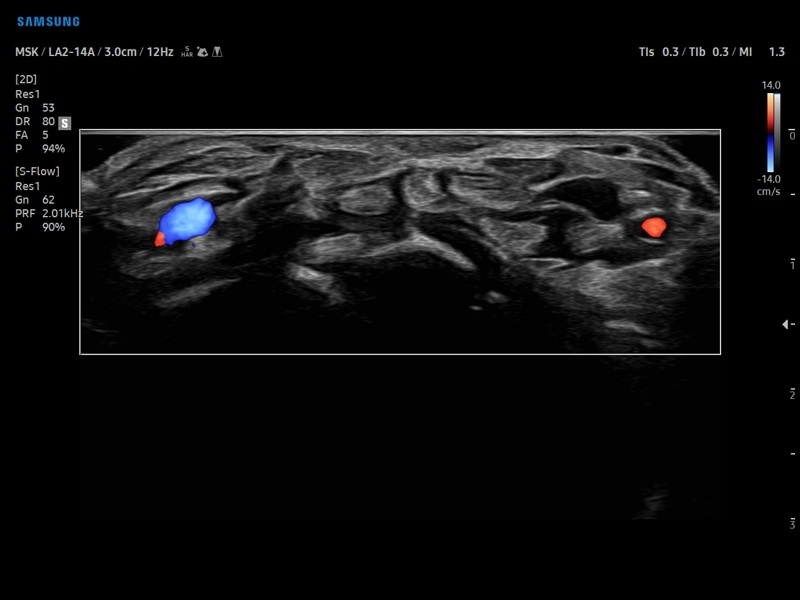

• Расширенная сосудистая визуализация: Auto IMT+, 2D Arterial Analysis

• Ангиология

• DPDI - двунаправленный энергетический допплер.